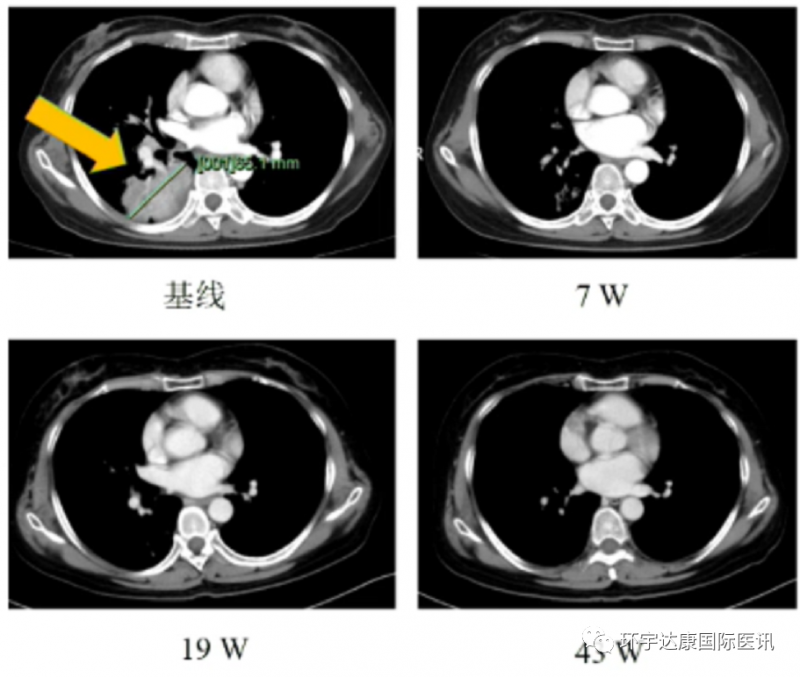

一位71岁的女性,确诊为ROS1阳性非小细胞肺癌合并脑转移,接受Taletrectinib治疗7周后病情达到客观缓解(PR),目前接受治疗5个月并仍在接受治疗。